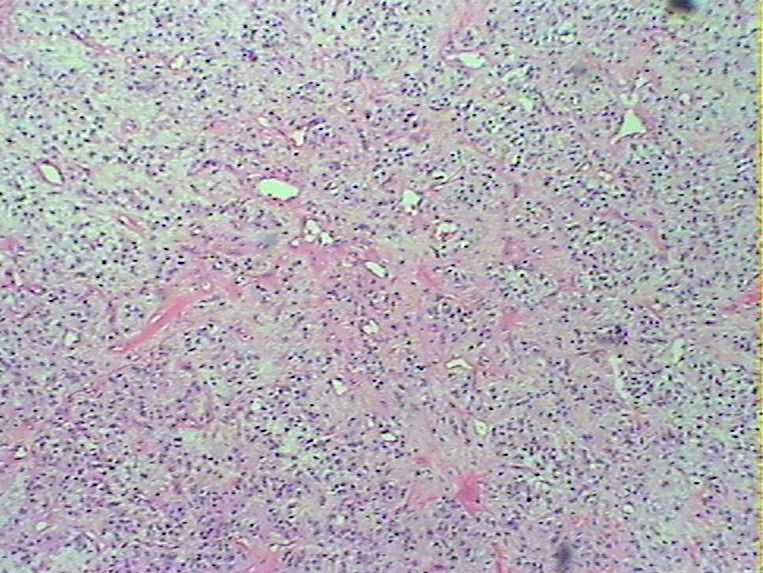

腹部肿物会诊血管球瘤

女45发现下腹部皮下肿物4个月

灰白色肿物一枚,9*8*5cm,切面实性、质韧,似有包膜

参考诊断

血管球瘤

会诊血管球瘤